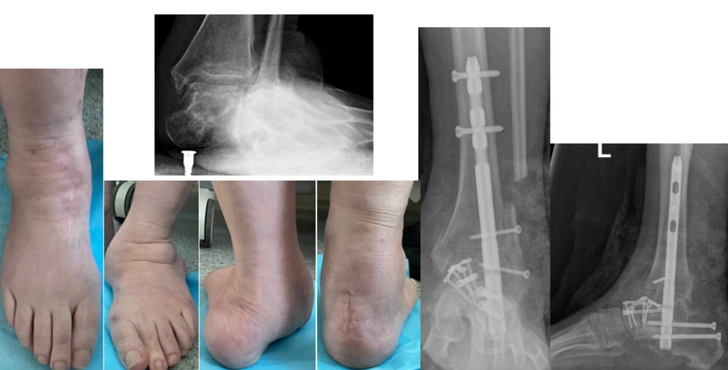

«Я жила обычной жизнью: занималась спортом, ходила на каблуках, ездила на машине. Потом постепенно шло искривление стоп, и в последние годы они стали загибаться внутрь. Так сильно, что я передвигалась буквально на костях, было очень больно», — рассказала Ирина.

Как показало обследование, у женщины была запущенная плосковальгусная деформация обеих стоп. Ступни были сильно «завалены» внутрь, суставы смещены. Наиболее частой причиной развития такого состояния становится врожденная слабость связочного аппарата. К этому могут привести и последствия травм, неврологические проблемы, а лишний вес и неудобная обувь лишь усугубляют ситуацию.

Ирина пыталась как-то исправить ситуацию самостоятельно. Женщина носила ортопедические стельки и специальную обувь. Однако на данной стадии проблема была уже анатомической: кости стояли неправильно. Исправить можно было только хирургическим путем.

Врачи вернули обеим стопам правильное положение и зафиксировали кости при помощи специальных конструкций, чтобы они срослись в нужной позиции. Обе операции прошли успешно, сейчас Ирина восстанавливается.